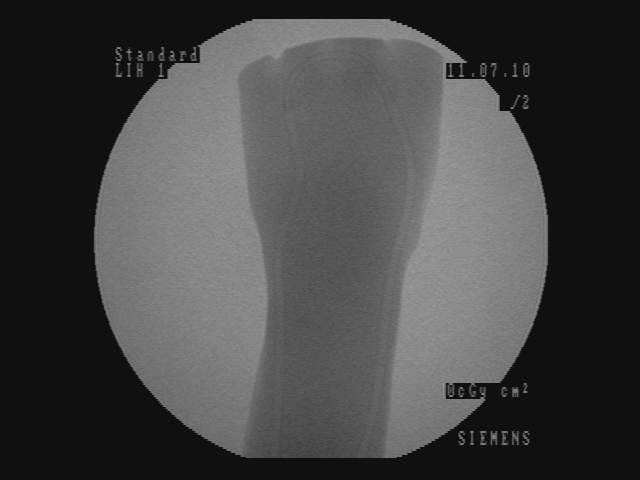

In Figure 5, for each scenario, one selected image Ilayerssubscript𝐼𝑙𝑎𝑦𝑒𝑟𝑠I_{layers} in the sequence can observed with different values of α𝛼\alpha, β𝛽\beta, γ𝛾\gamma and δ𝛿\delta. Each row i𝑖i corresponds to the sequence i𝑖i. From left to right, the layer visualized in Ilayerssubscript𝐼𝑙𝑎𝑦𝑒𝑟𝑠I_{layers} is getting closer to the X-ray source viewpoint. In the column (a), the furthest layer (the X-ray image) is displayed. In the column (b), the second layer (the background), in the column (c), the blending of the front layer with the background, in the column (d), the blending of the three layers and finally, in the column (e), the closest layer is shown. Additional images from the sequences can be visualized in the supplementary video where interaction between the layers by changing the blending values can be observed.

(a) (α,β,γ,δ)=(0,0,1,1)𝛼𝛽𝛾𝛿0011(\alpha,\beta,\gamma,\delta)=(0,0,1,1)

Refer to caption

(b) (α,β,γ,δ)=(0,1,0,0)𝛼𝛽𝛾𝛿0100(\alpha,\beta,\gamma,\delta)=(0,1,0,0)

(c) (α,β,γ,δ)=(0.4,0.6,0,0)𝛼𝛽𝛾𝛿0.40.600(\alpha,\beta,\gamma,\delta)=(0.4,0.6,0,0)

(d) (α,β,γ,δ)=(0.2,0.3,0.5,0.5)𝛼𝛽𝛾𝛿0.20.30.50.5(\alpha,\beta,\gamma,\delta)=(0.2,0.3,0.5,0.5)

(e) (α,β,γ,δ)=(1,0,0,0)𝛼𝛽𝛾𝛿1000(\alpha,\beta,\gamma,\delta)=(1,0,0,0)

(f) Inpainting

Figure 5: Per row i𝑖i, multi-layer image Ilayerssubscript𝐼𝑙𝑎𝑦𝑒𝑟𝑠I_{layers} of one selected frame in the sequence i𝑖i with different blending parameters (α,β,γ,δ)𝛼𝛽𝛾𝛿(\alpha,\beta,\gamma,\delta)

Similar to results from Habert et al. [6], the images resulting from synthesization are not as sharp as a real video image. The area synthesized by our algorithm is approximately 20 cm ×\times 20 cm (C-arm detector size), which is small compared to the wide-angle field of view from the Kinect v2. Reduced to the area of synthesization, the video and depth from Kinect is not of high resolution enough for sharper results. More specialized hardware with smaller field of view and higher resolution RGBD data would solve this problem. Moreover, several artifacts can be seen around the hand and surgical instruments in the synthesized image due to high difference and noise in depth in the RGBD data from the 2 cameras. However, our results demonstrate that our method is working well, since the incision line and cross drawn on the hand model and patient hand are perfectly visible in the recovered background image and can be seen in transparency through the hands and surgical tools in the images of Figure 5-column (c) and (d). In the scalpel sequence (sequence 6) in Figure 5-column (b), it can be seen that the tip of the scalpel is considered as background, this is due to the margin of few centimeters used for background segmentation. In this image, the scalpel is actually touching the skin.